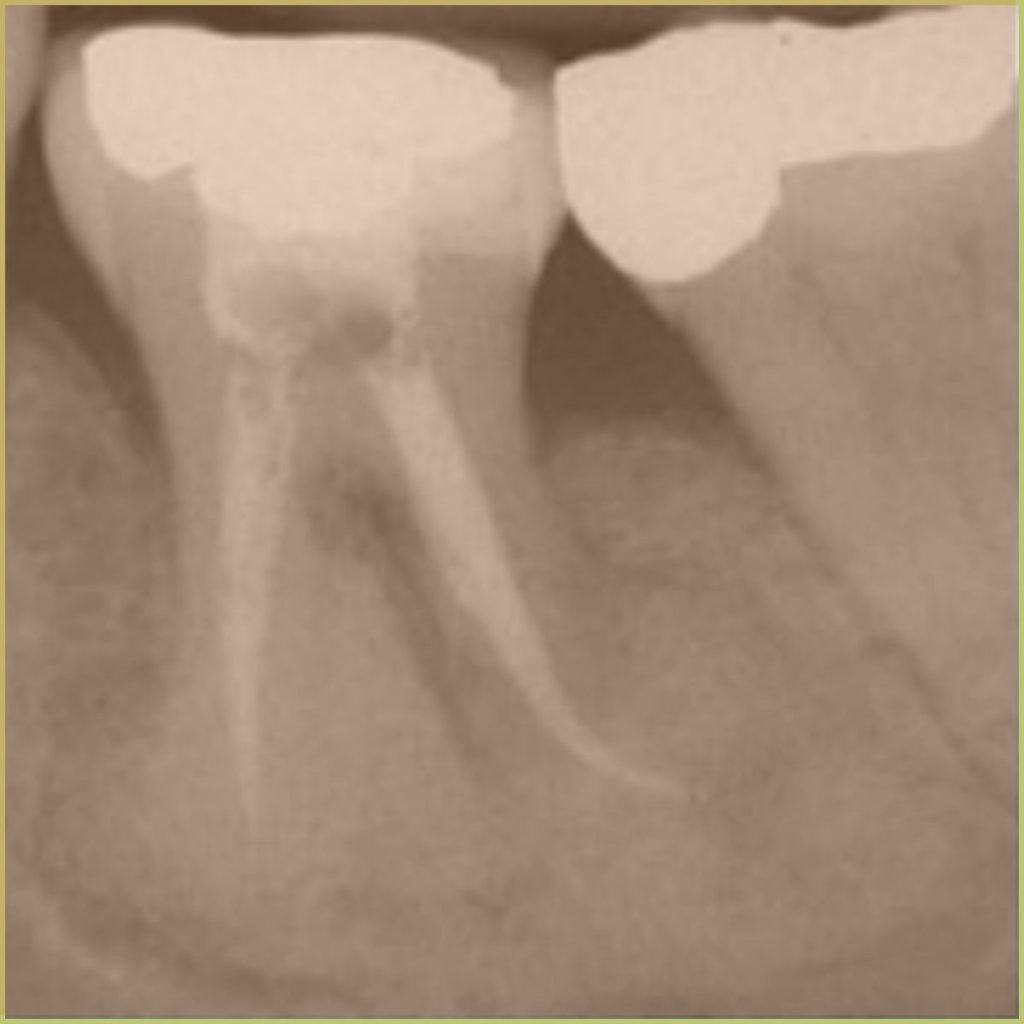

Cementoblastoma is a rare benign mesenchymal tumor of odontogenic origin. It most commonly involves the mandibular permanent first molar area. Teeth with associated lesions remain vital. The common clinical presentation includes:

- Well-circumscribed radiopaque lesion with peripheral radiolucent halo.

- Mass fused to the root of the affected tooth.

- Possible root resorption, invasion of the root canal, and cortical erosion.